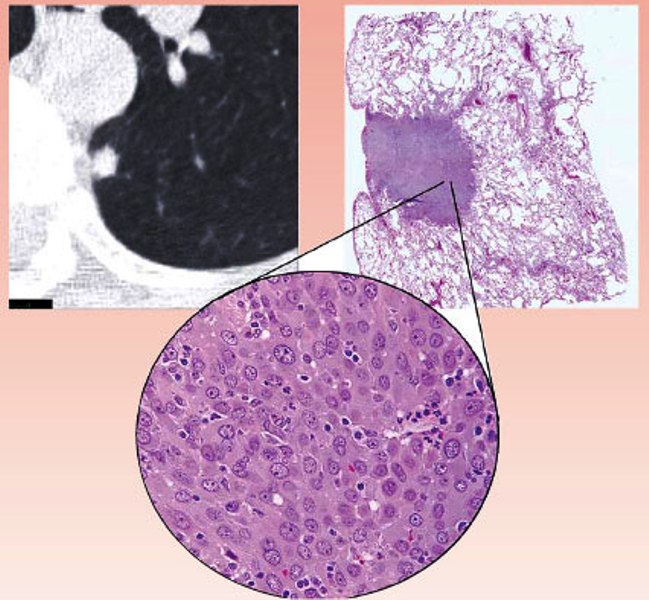

Milano e Ingelheim, 11 ottobre 2010 – Boehringer Ingelheim ha annunciato oggi i risultati promettenti di due studi clinici in ambito oncologico, condotti sul suo farmaco sperimentale, afatinib (BIBW 2992), presentati in occasione del 35esimo Congresso della Società Europea di Oncologia Medica (ESMO) a Milano. I risultati dello studio di Fase III, LUX-Lung 1, suggeriscono che afatinib sia molto attivo in pazienti con carcinoma polmonare non a piccole cellule (NSCLC)1 in stadio avanzato, mentre nello Studio di Fase II, LUX-Lung 2, afatinib ha mostrato un beneficio in termini di sopravvivenza in pazienti con NSCLC avanzato che presentavano una mutazione del gene per il recettore del fattore di crescita epidermico (EGFR).

Lo studio LUX-Lung 1 (fase II b/III) ha confrontato afatinib a placebo in più di 580 pazienti con NSCLC avanzato, che avevano manifestato una progressione di malattia a seguito di almeno un trattamento chemioterapico e di un EGFR-TKI di prima generazione (erlotinib o gefitinib) con i seguenti risultati1:

- Pur non avendo raggiunto l’endpoint primario della sperimentazione nell’aumento della sopravvivenza complessiva (overall survival, OS), afatinib ha ritardato in maniera significativa la ripresa della progressione del tumore, triplicando il periodo di sopravvivenza libero da progressione di malattia (progression-free survival, PFS, endpoint secondario) rispetto a placebo (3,3 mesi vs 1,1 mesi);

- Il beneficio in termini di PFS è stato evidente e significativo in tutti i sottogruppi di pazienti, come confermato dall’esame indipendente di un gruppo di esperti;

- Si è avuta una percentuale significativamente superiore di controllo o riduzione della massa tumorale (disease control rate, DCR) nei pazienti che assumevano afatinib (DCR: 58%) rispetto a placebo (DCR: 18%);

Il tumore polmonare è la forma di cancro più diffusa e letale al mondo. Ogni anno 1,6 milioni di persone si ammalano di tumore al polmone e 1,4 milioni muoiono4 a causa di esso. Questa patologia rappresenta un’area in cui la medicina non è stata ancora in grado di dare una risposta risolutiva, soprattutto per i casi in stadio avanzato, quando il tumore è particolarmente aggressivo e le opzioni terapeutiche disponibili per i pazienti sono limitate. Al momento non esiste alcuna terapia approvata per i pazienti con tumore polmonare in stadio avanzato per i quali la chemioterapia non abbia avuto successo e il tumore sia progredito dopo il trattamento con EGFR-TKI di prima generazione.